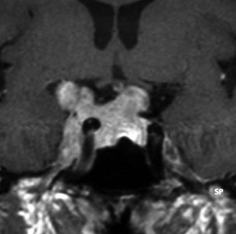

左は下垂体腺腫(緑の腫瘍)が内頚動脈に挟まれていることを示しています。

中央は手術前の下垂体腺腫で,視神経も正常下垂体も位置はわかりません。

右は手術翌日の画像です。黄色の矢印の先が残した正常下垂体組織です。桃色の矢印の先に視神経(視交叉)がはっきり見えています。術後の一時的な尿崩症がありました。クモ膜が残っているので髄液漏は生じませんでした。でも正常下垂体組織(黄色矢印)も視交叉も腫瘍に圧迫されてペラペラになっていますから,いつもうまく行くとは限りません。